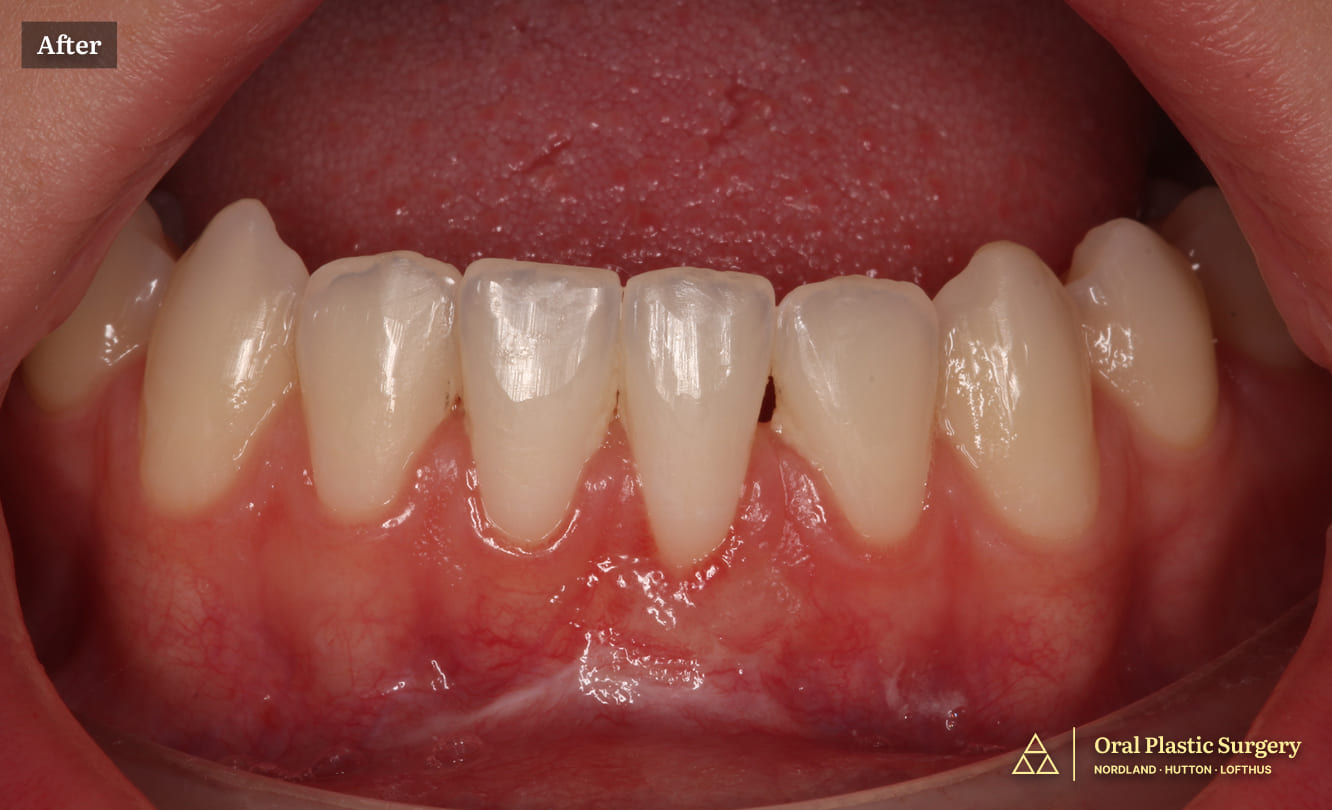

Improved tooth proportions and stable gingival symmetry after microsurgical crown lengthening, natural tooth structure revealed

The outcome was dramatic, yet completely natural.

By removing excess gum tissue and carefully refining the underlying architecture, Dr. Hutton was able to reveal the healthy tooth structure that had been hidden for years.

The final result created:

• Cleaner smile proportions

• A more balanced gumline

• A brighter, more confident appearance, without changing the teeth themselves

The patient’s smile now looks harmonious and timeless, with a result designed to remain stable long-term.

More natural tooth display and balanced gumline after single-visit smile makeover surgery. Teeth appear properly proportioned without any restorative work